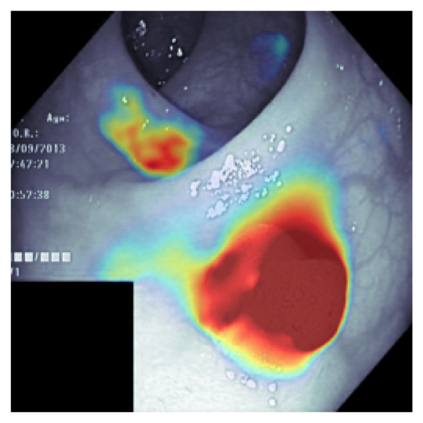

The sigmoid activation is the standard output activation function in binary classification and segmentation with neural networks. Still, there exist a variety of other potential output activation functions, which may lead to improved results in medical image segmentation. In this work, we consider how the asymptotic behavior of different output activation and loss functions affects the prediction probabilities and the corresponding segmentation errors. For cross entropy, we show that a faster rate of change of the activation function correlates with better predictions, while a slower rate of change can improve the calibration of probabilities. For dice loss, we found that the arctangent activation function is superior to the sigmoid function. Furthermore, we provide a test space for arbitrary output activation functions in the area of medical image segmentation. We tested seven activation functions in combination with three loss functions on four different medical image segmentation tasks to provide a classification of which function is best suited in this application scenario.